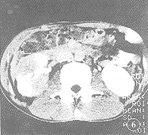

圖3圖4 右腎炎性腫塊,平掃右腎中下極前方等密度腫塊腎盂閉塞

圖5 同圖4病例。增強掃描呈實性腫塊,中心有斑片樣低密度灶

圖4急性腎葉性腎炎增強掃描具有典型、特徵性表現,即病變呈楔形或扇形的低密度“葉性損害”,如累及多個腎葉,則可觀察到多個類似的病灶。成熟的腎膿腫呈圓形或橢圓液性低密度灶,有完整的膿腫壁,厚薄均勻,增強掃描壁有明顯強化。未成熟的腎及腎周圍膿腫的診斷有時會遇到困難,增強掃描呈類圓形或不規則狀的“非葉性損害”,有中度不均一強化,如發現腎周圍間隙內有較明顯的液性低密度區及周邊的膿腫壁,腎筋膜和橋隔增厚等徵象,診斷不難成立。如病灶僅有中心部分,且較小的不規則液化壞死區則須注意和腎癌鑑別。腎臟炎性腫塊的診斷困難,平掃及增強表現為腎臟及其相對應腎周圍間隙內的局限性、實質性腫塊,有明顯的占位效應及中度不均一強化,和腎癌表現類似,其診斷應密切結合臨床。